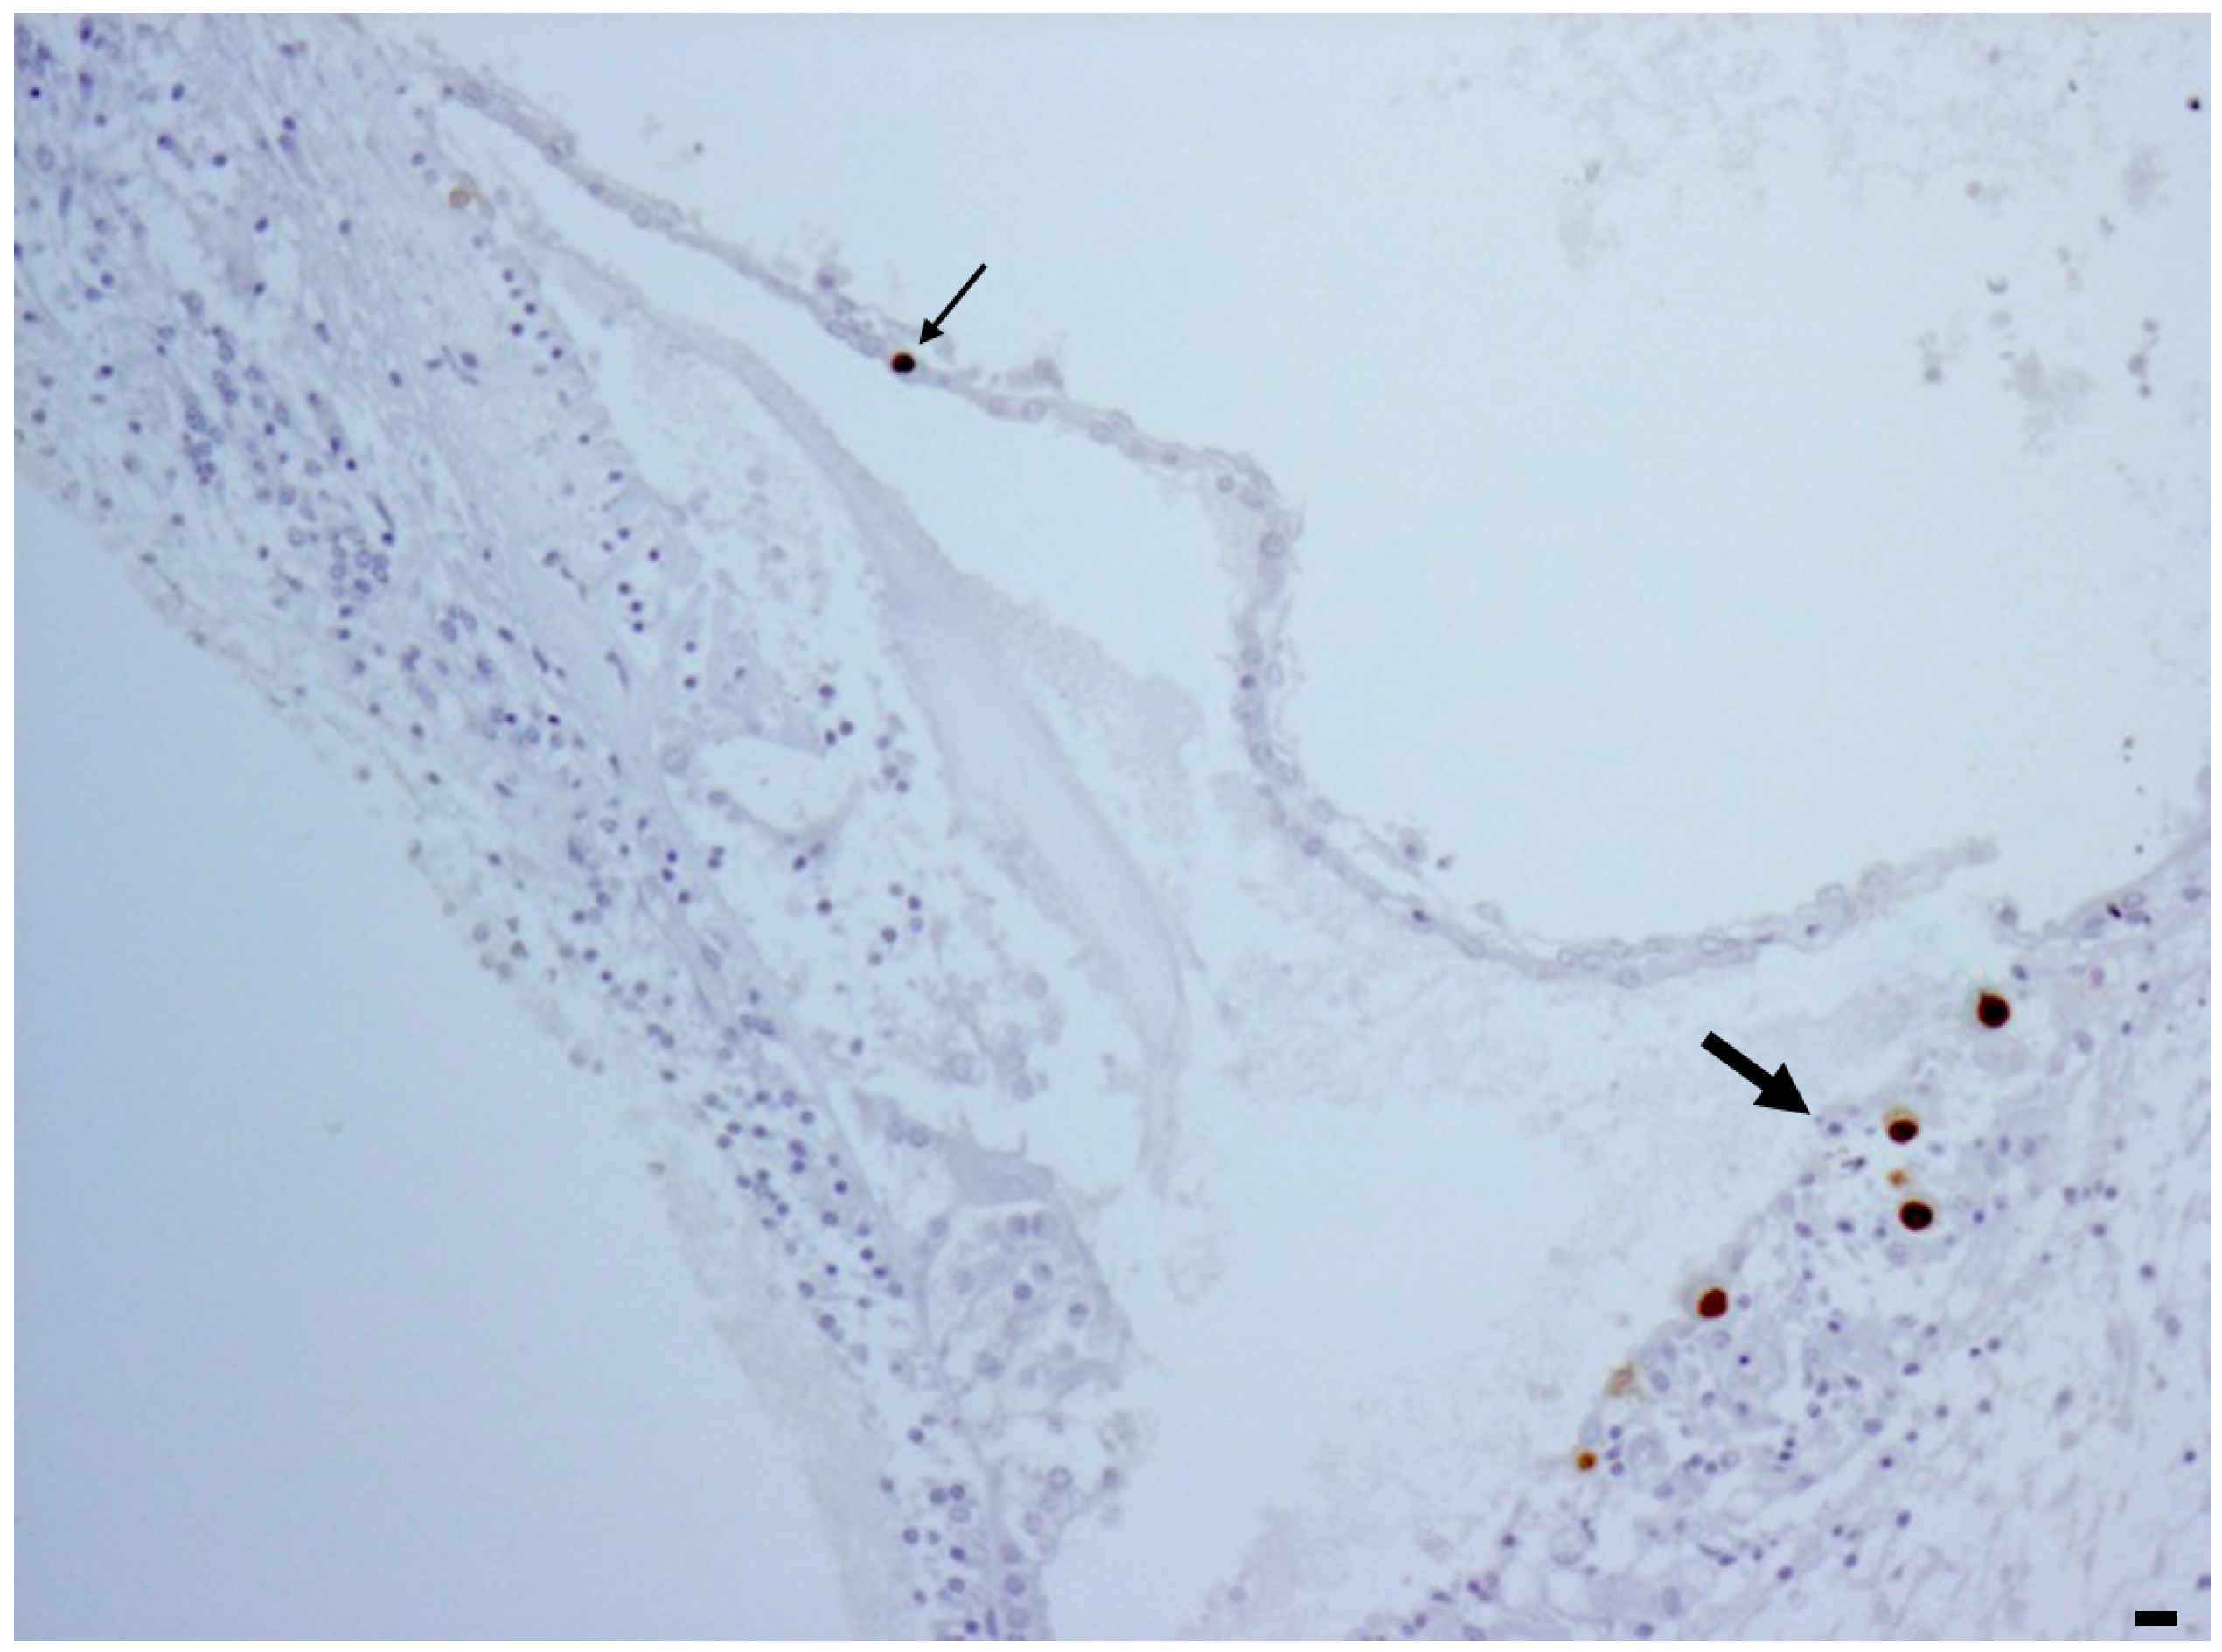

1. Introduction

2. Results

2.1. Temporal Lobe

2.2. Inner Ear